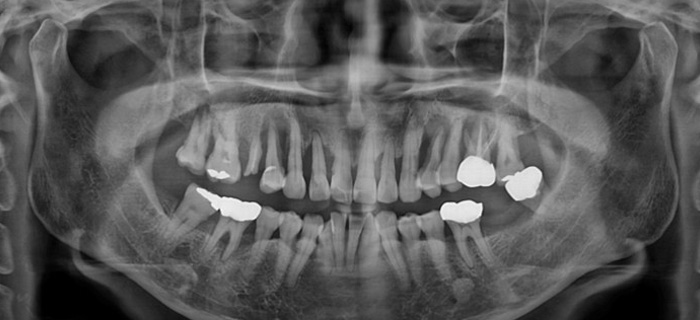

치아가 빠졌거나

어금니가 없으신 분